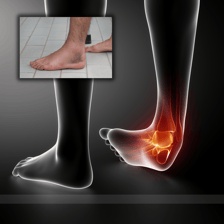

Esguinces y Desgarros Ligamentosos

Origen: Se producen cuando los ligamentos que conectan los huesos en una articulación son estirados o desgarrados, típicamente debido a torceduras o golpes fuertes.

Tratamiento: Deben inmovilizarse con vendajes elásticos o compresivos para controlar la inflamación. En algunos casos, las férulas blandas pueden proporcionar soporte adicional.